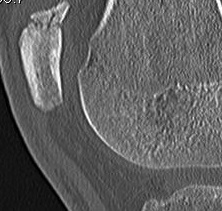

Malunion Patella Fractures

Partial patellectomy

- remove part of medial or lateral facet

- good functional and pain relief

Non Union Patella Fragment